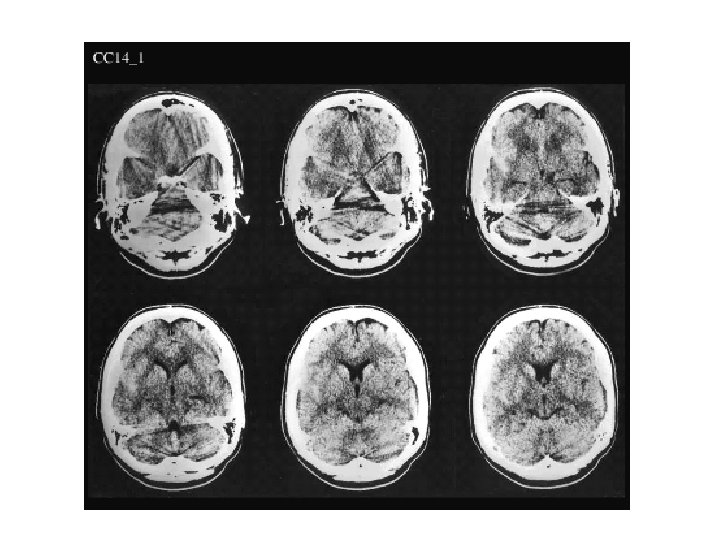

- Slides: 23